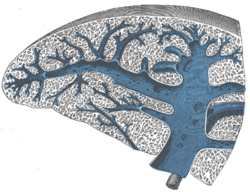

Horizontal disposition of the peritoneum in the upper part of the abdomen. Transverse section of the spleen, showing the trabecular tissue and the splenic vein and its tributaries.

Transverse section of the spleen, showing the trabecular tissue and the splenic vein and its tributaries. Back of lumbar region, showing surface markings for kidneys, ureters, and spleen.